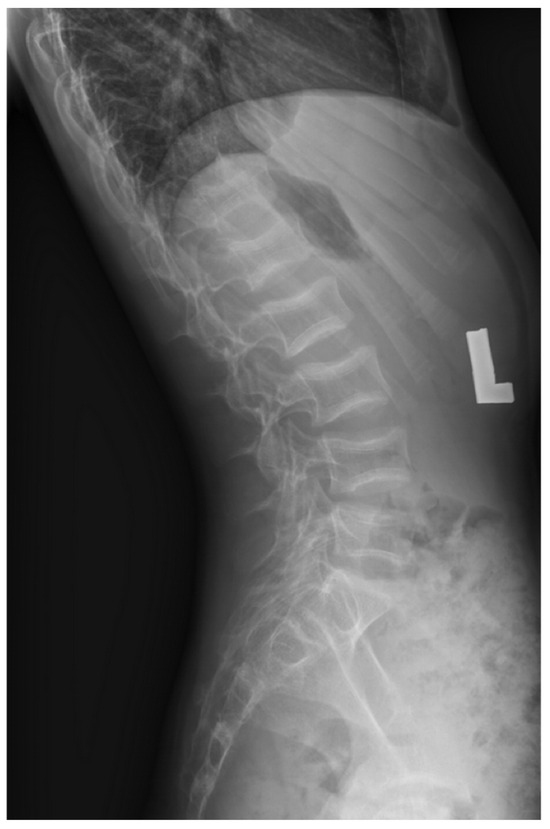

| Patient No. | DXA Z-Score Spine with Height-Adjustment in Case of Short Stature | DXA Z-Score TBLH with Height-Adjustment in Case of Short Stature | Identified Vertebrae Fractures | Other Identified Fractures | Implemented Treatment |

|---|---|---|---|---|---|

| 1 | −1.70 HAZ = −0.72 | −3.70 HAZ = −2.16 | Th7, Th11, L1 | Forearm | bisphosphonate therapy + calcium, vitamin D |

| 2 | −3.90 HAZ = −1.46 | −8.00 HAZ = −5.65 | Th5-Th12, L1-L4 | - | bisphosphonate therapy + calcium, vitamin D |

| 3 | −3.20 HAZ = −2.25 | −4.20 HAZ = −3.20 | C7, Th5, Th7-Th12, L1, L3, L4 | Sternum | bisphosphonate therapy + calcium, vitamin D |

| 4 | −2.60 | −1.20 | L1 | Tibia | bisphosphonate therapy + calcium, vitamin D |

| 5 | −1.30 | −0.70 | Th12, L1 | Forearm (2013), (2017) | bisphosphonate therapy + calcium, vitamin D |

| 6 | −3.50 | −4.90 | Th12, L1 | Femur, shoulder | bisphosphonate therapy + calcium, vitamin D |

| 7 | −3.10 | −2.30 | Multilevel vertebral fractures (thoracic and lumbar vertebrae) | - | bisphosphonate therapy + calcium, vitamin D |

| 8 | −2.70 | −3.30 | Th5-Th9, L4, L5 | - | bisphosphonate therapy + calcium, vitamin D |

| 9 | −5.50 HAZ = −4.60 | −4.50 HAZ = −3.49 | Th9, Th11, L1 | - | endoscopic transsphenoidal surgery of pituitary adenoma; parental refusal for introducing bisphosphonate treatment; calcium + vitamin D |

| 10 | −1.80 | −1.00 | Th11-L3 | - | vitamin D |

| 11 | −4.30 | −3.50 | Th11-L5 | Humerus | bisphosphonate therapy + calcium, vitamin D |